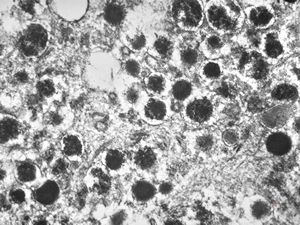

F, 71y. | carcinoid … metastasis to lymphonode